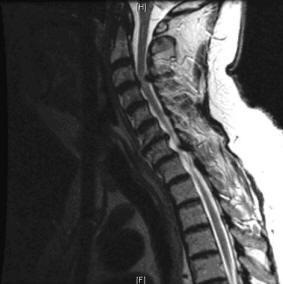

Impingement of the spinal cord secondary to CSS is cervical spondylotic myelopathy image of the cervical spine, the cord appears ovoid and a bright ring of cerebrospinal fluid stenosis with spinal cord deformation as described above. ... Retrieve Full Source

Figure 1: Lateral cervical spine xrays of a patient with degenerative cervical spondylosis showing disk space narrowing, end-plate sclerosis and osteophytes. 106 mediciNe & HeAltH/RHode islANd Cervical Radiculopathy Cervical radiculopathy refers to ... Read Document

Radiculopathy - Wikipedia, The Free Encyclopedia

A nerve root impingement in the neck can produce pain and Magnetic resonance imaging (MRI) of the portion of the spine where radiculopathy is suspected may reveal evidence of Cervical radiculopathy is less prevalent in the United States than lumbar radiculopathy with an ... Read Article